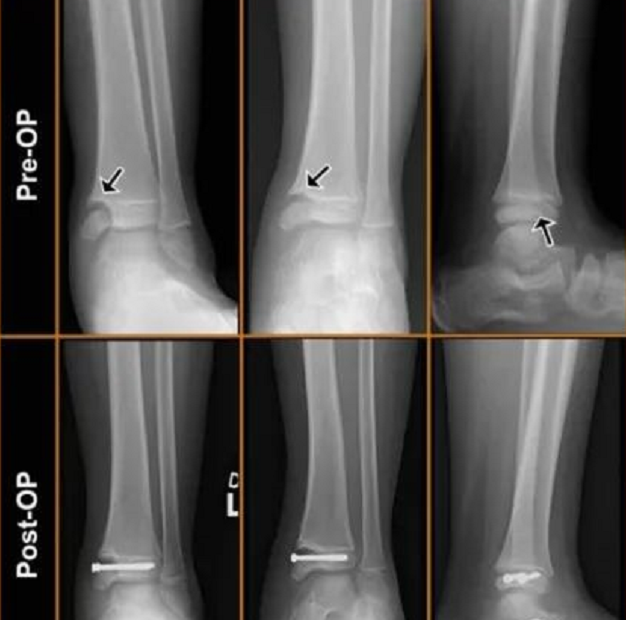

回答病情分析 根据你的描述,分析你的右内踝,腓骨下段发生了骨折,已经采用内固定的方法治疗了 指导意见 但是在复查X光片子的时候,发现腓骨上段以前骨折过,已经愈合了腓骨是人体承受重量较少的骨骼,骨折后有可能因为症状轻微而不被发现;右腓骨下端骨折的处理方法主要取决于骨折的移位情况移位明显的骨折解剖复位需要进行解剖复位,以恢复踝关节的平整和匹配内固定进行较稳且牢靠的内固定,确保骨折部位稳定术后锻炼术后鼓励患者早期进行踝关节功能锻炼,预防关节粘连和僵硬未发生明显移位的骨折保守治疗若踝关节结构完整且踝穴较稳定,可采用保守治;年轻的话骨折最好是手术治疗,恢复快并且对本身功能要求高。

如果腓骨下端骨折移位明显,导致踝关节不稳定或踝关节移位严重,这种情况较为严重,不能通过保守治疗解决,需要手术治疗使骨折复位,并进行石膏外固定综上所述,腓骨下端骨折的严重程度取决于其是否影响踝关节的稳定性在不影响稳定性的情况下,骨折相对不严重而在影响稳定性的情况下,骨折则较为严重,需要手术治疗;腓骨下端是人体踝关节构成部分,患者在发生腓骨下端骨折后,若移位明显则会影响踝穴稳定性,需进行复位和有效固定,否则可能导致踝关节创伤性关节炎的发生并遗留明显后遗症因此对于移位明显的腓骨下端骨折,患者需进行解剖复位以恢复踝关节的平整和匹配,同时进行较稳且牢靠的内固定术后鼓励患者早期进行踝;对肢体的功能影响也较小三腓骨下13骨折 治疗方案需要良好的复位,可采用手术或手法复位,并进行夹板固定石膏固定,以及钢板螺丝钉内固定 原因腓骨下13尤其是外踝部位参与构成了踝穴,骨折后踝穴会发生改变,导致踝关节失稳疼痛,甚至引发创伤性关节炎,因此必须确保良好的复位;腓骨骨折手术钢板内固定后需要继续功能锻炼首先把患肢抬高,用软枕头把患肢垫高,这样有利于患肢的血液回流,利于肿胀的消退,嘱咐患者家属帮助多做腿部肌肉组织的按摩,防止肌肉萎缩发生患肢关节的屈曲和伸直的主动运动,以防止关节的僵硬黏连一个月后进行复查,若无明显的异常,有骨痂的形成可在;临床上骨折局部无水肿无压痛无异常活动X线膜内骨化部分两端会合,软骨骨化也连成一体,骨痂呈梭形,但骨折线可见,此期已达临床愈合伤后1012周,临床上此期骨折愈合很牢固,患肢可以开始使用3骨痂改造塑形期在应力作用下,骨痂改建塑形,骨髓腔再通,恢复骨的原形再说一下,谁说的“。